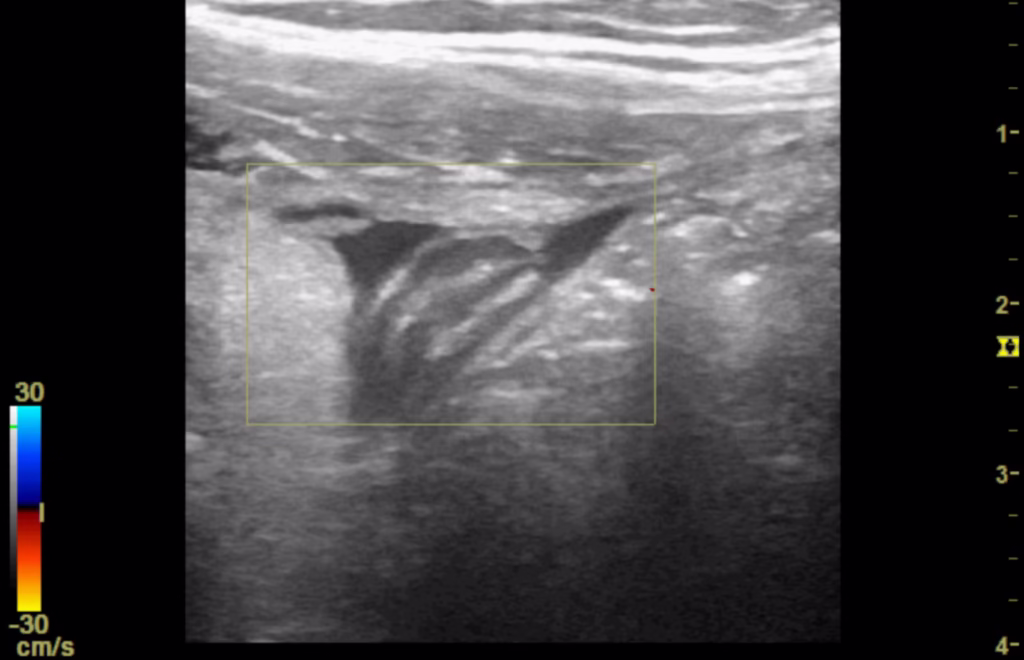

Figure 4. Point of care ultrasound (POCUS) image of right iliac fossa using the high frequency 12 MHz linear probe. This shows a small anechoic region felt to be consistent with a pocket of free fluid. There is degree of colour Doppler enhancement within the central component.

His vital signs remained stable and repeat blood tests were as follows: WBC 7.92 x 109, neutrophils 3.59 x 109, CRP 5.2 mg/L. Repeat POCUS was performed which demonstrated progressive hyperinflammatory, echogenic changes and a moderate amount of localised free fluid. Within this free fluid there appeared to be a blind ending tubular structure without peristalsis measuring 0.61 cm in diameter. While there was no colour Doppler enhancement, this area was consistent with significant sonographic tenderness (See Figures 5-8).